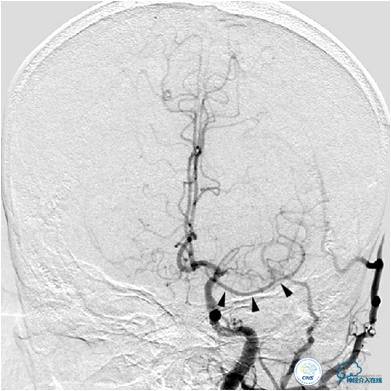

图2:患者右侧颈内动脉造影提示右侧大脑中动脉次全闭塞,血流缓慢。大脑前动脉未见显影。

图3A:左侧颈总动脉造影动脉期,看到异常血管代偿供应左侧大脑中动脉分布区(箭头),双侧大脑前动脉双干显示。